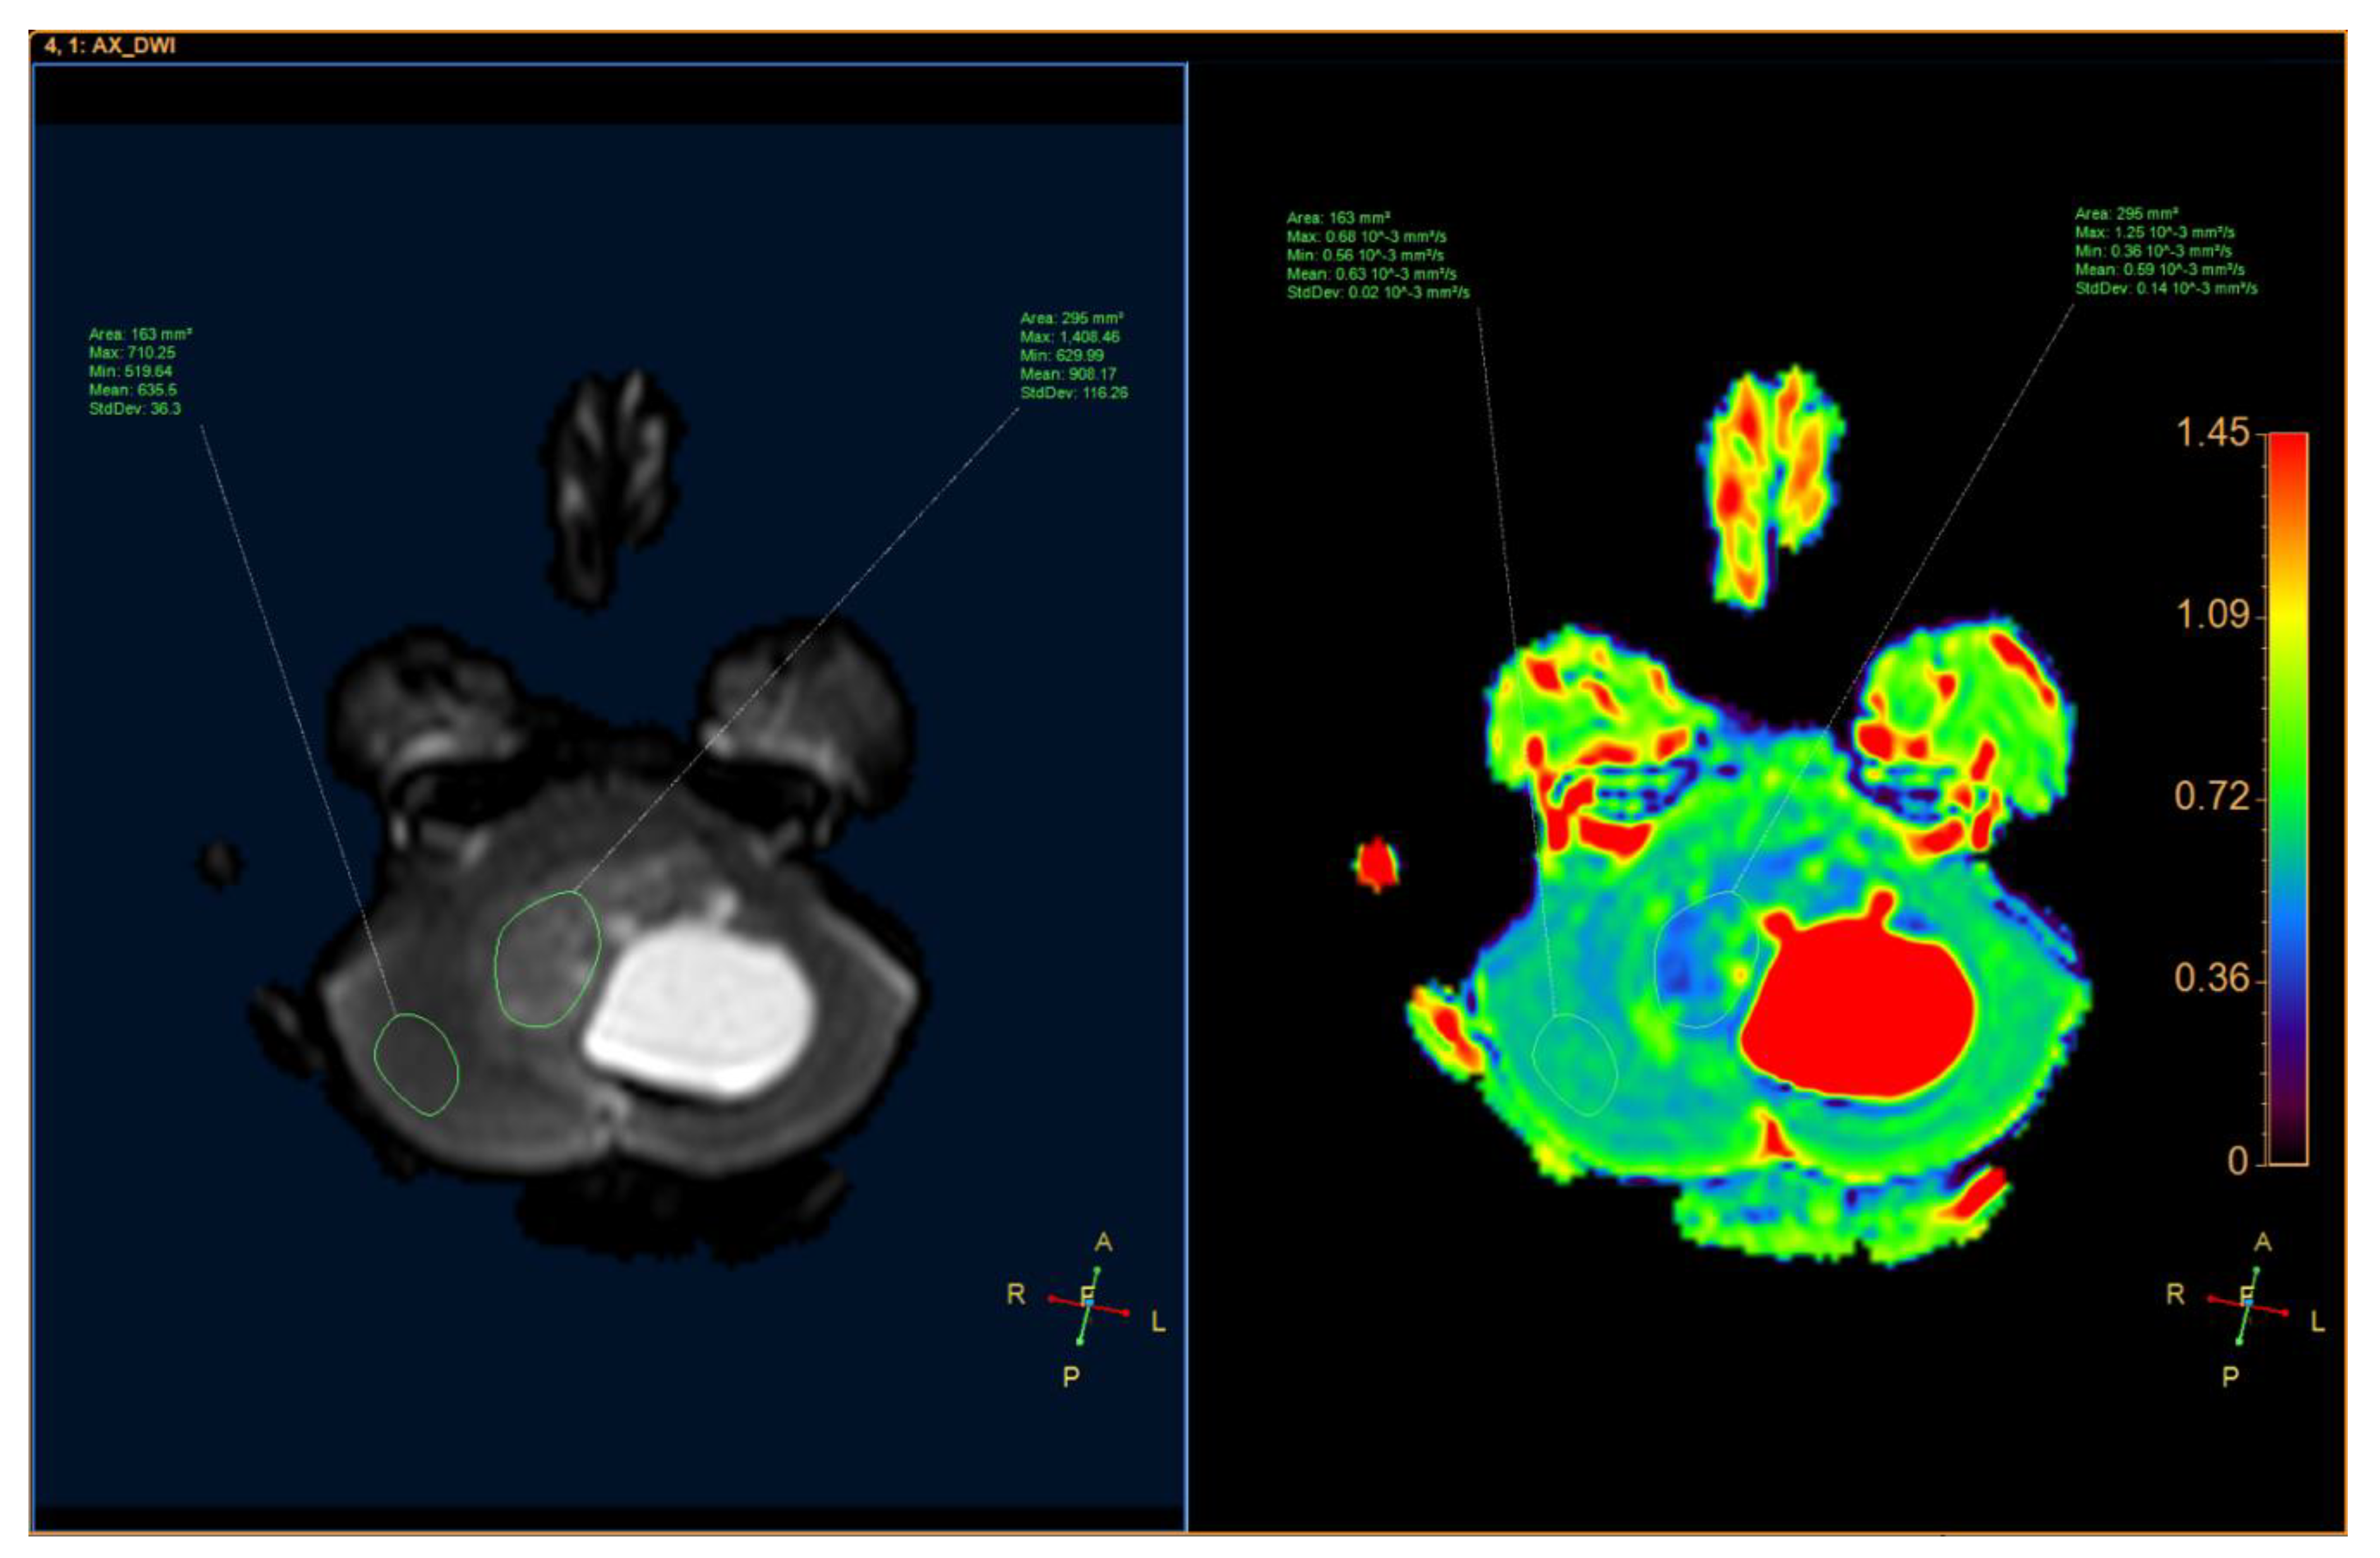

2. Case Presentation